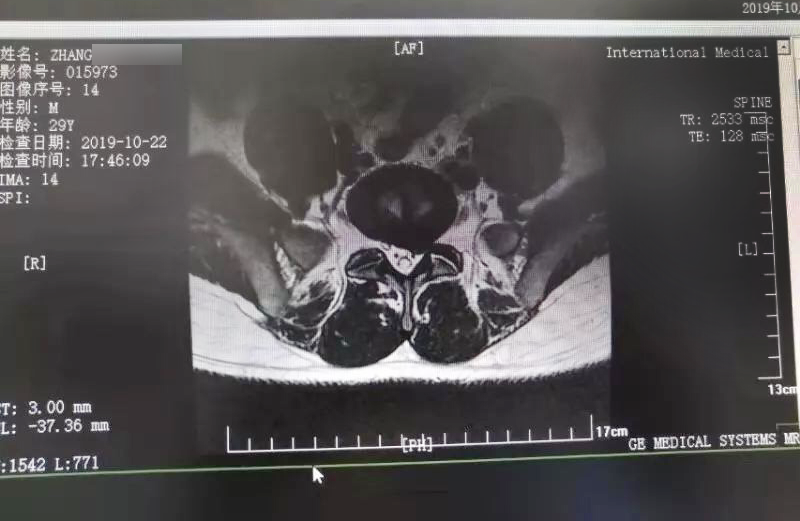

三秦網(wǎng)報道—西安國際醫(yī)學(xué)中心骨科醫(yī)院成功完成首例椎間孔鏡手術(shù)

三秦網(wǎng)報道—西安國際醫(yī)學(xué)中心骨科醫(yī)院成功完成首例椎間孔鏡手術(shù)。點擊閱讀。